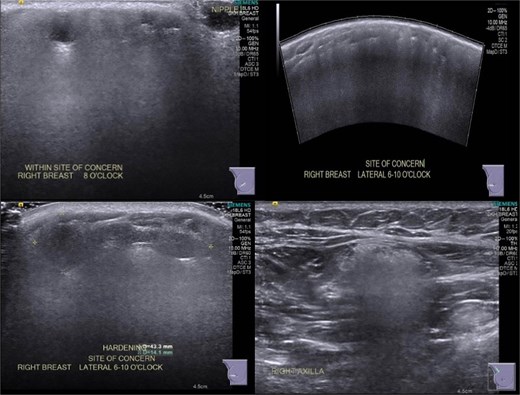

In June 2021, after 6 months of the breast lump increasing in size and pain, she sought a second opinion. Examination showed a firm and mobile right breast mass 120 × 80 mm from 6 to 11 o’clock position. Repeat ultrasound showed diffuse ill-defined hyperechoic areas with posterior shadowing throughout the right breast, with superficially located cystic areas, in keeping with silicone granulomata and oil cysts (Fig. 6). A superficially located ill-defined hypoechoic area measuring 43 × 14 × 32 mm corresponded to the palpable lesion. Several right axillary lymph nodes were hyperechoic with posterior shadowing in keeping with silicone deposition. Magnetic resonance imaging (MRI) breast was offered given the non-diagnostic routine imaging, along with option of excision biopsy of the enlarging symptomatic lump.

June 2021: Repeat ultrasonography showing silicone granulomata.